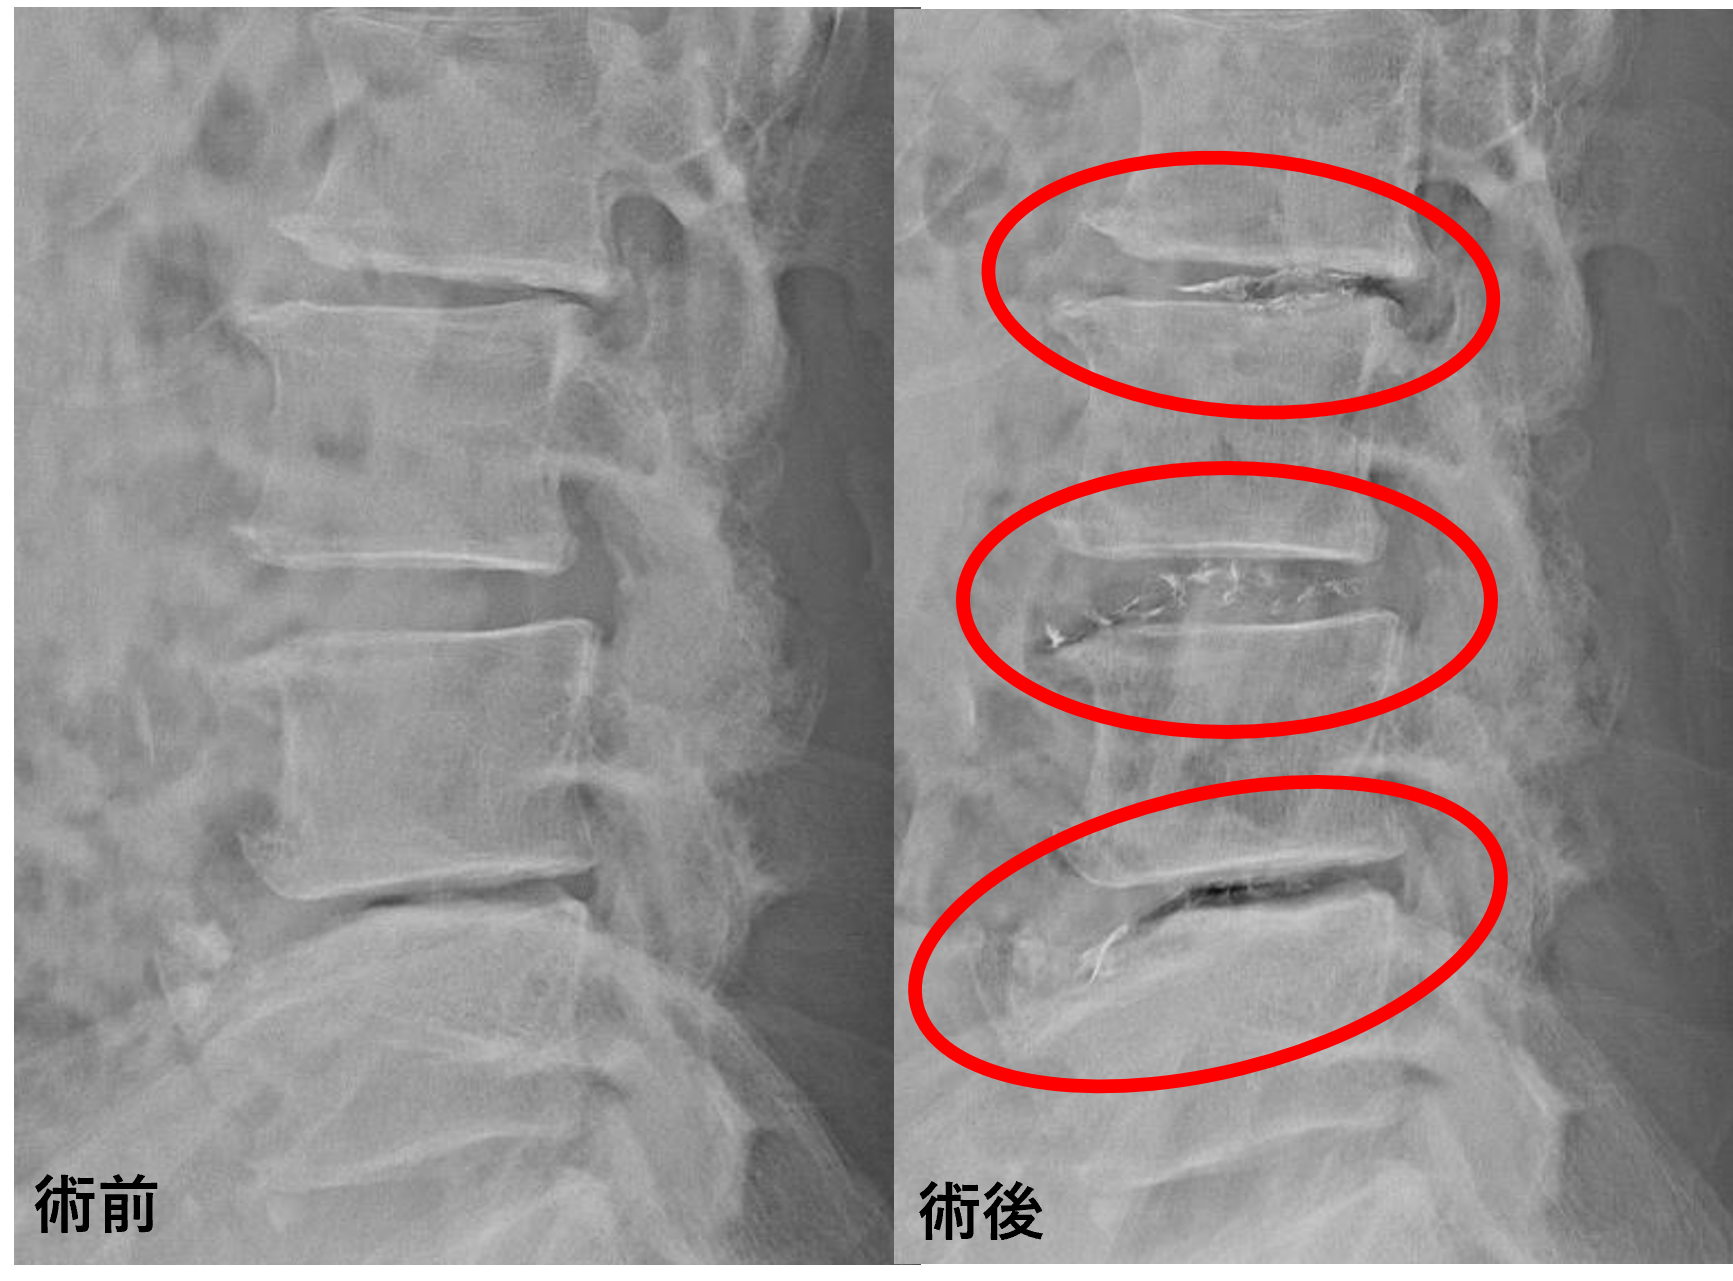

画像及び所見について

- L2/3 – 椎間板変性、膨隆、椎間孔狭窄、脊柱管狭窄症術後

- L3/4 – 椎間板変性、椎間板ヘルニア、椎間孔狭窄、脊柱管狭窄症術後

- L4/5 – 椎間板変性、椎間板ヘルニア、椎間孔狭窄、終板変性

以上のことが画像上認められました。

L2/3、3/4、4/5の椎間板所見による脊柱管の圧排が、症状の原因の可能性が高い。

患者様と相談の元、L2/3、3/4、4/5にセルゲル法を施行